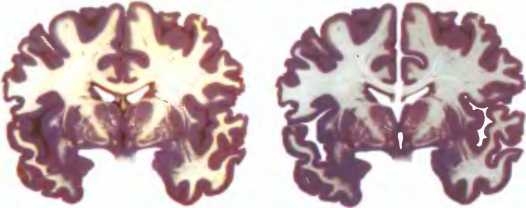

Странное полузнание пациентки V. Р. о только что пережитом связано со странным и редким повреждением: ее мозг был, по сути, разделен надвое хирургическим путем. Эта серьезная операция была проведена для избавления пациентки от очень тяжелой формы эпилепсии. Перерезание связей между нейронами двух полушарий остановило передачу с одного полушария на другое вспышек беспорядочной электрической активности, вызывавших эпилептические припадки и до операции охватывавших весь мозг пациентки. В результате активность, вызывающая припадки, оказалась ограничена одной половиной мозга, и это облегчило участь больной. Однако пациентке (как и многим другим людям, перенесшим подобные операции) пришлось заплатить за это, став жертвой одного из самых причудливых в неврологической практике побочных эффектов.

У пациентов с разделенным головным мозгом зрительная информация не может выходить за пределы одного полушария. В итоге, если не двигать глазами, каждое полушарие получает лишь информацию о противоположной стороне поля зрения. Внизу. Головной мозг разделяют, перерезая часть мозолистого тела.